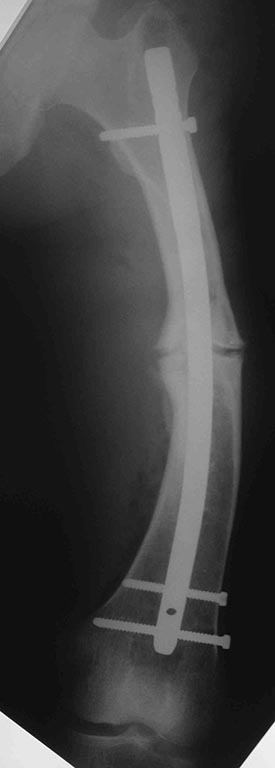

Maxim Agalakov 23 Июль 2014, 15:35

Сегодняшние снимки из операционной, подходящей пластины не было, а гвоздь был.

Максим, великолепно, поздравляю!

A что за гвоздь-то?

Stryker S2 длина 280мм, диаметр 12мм

Stryker s2 универсальный,custom made,диаметр 12, не канюлированный.